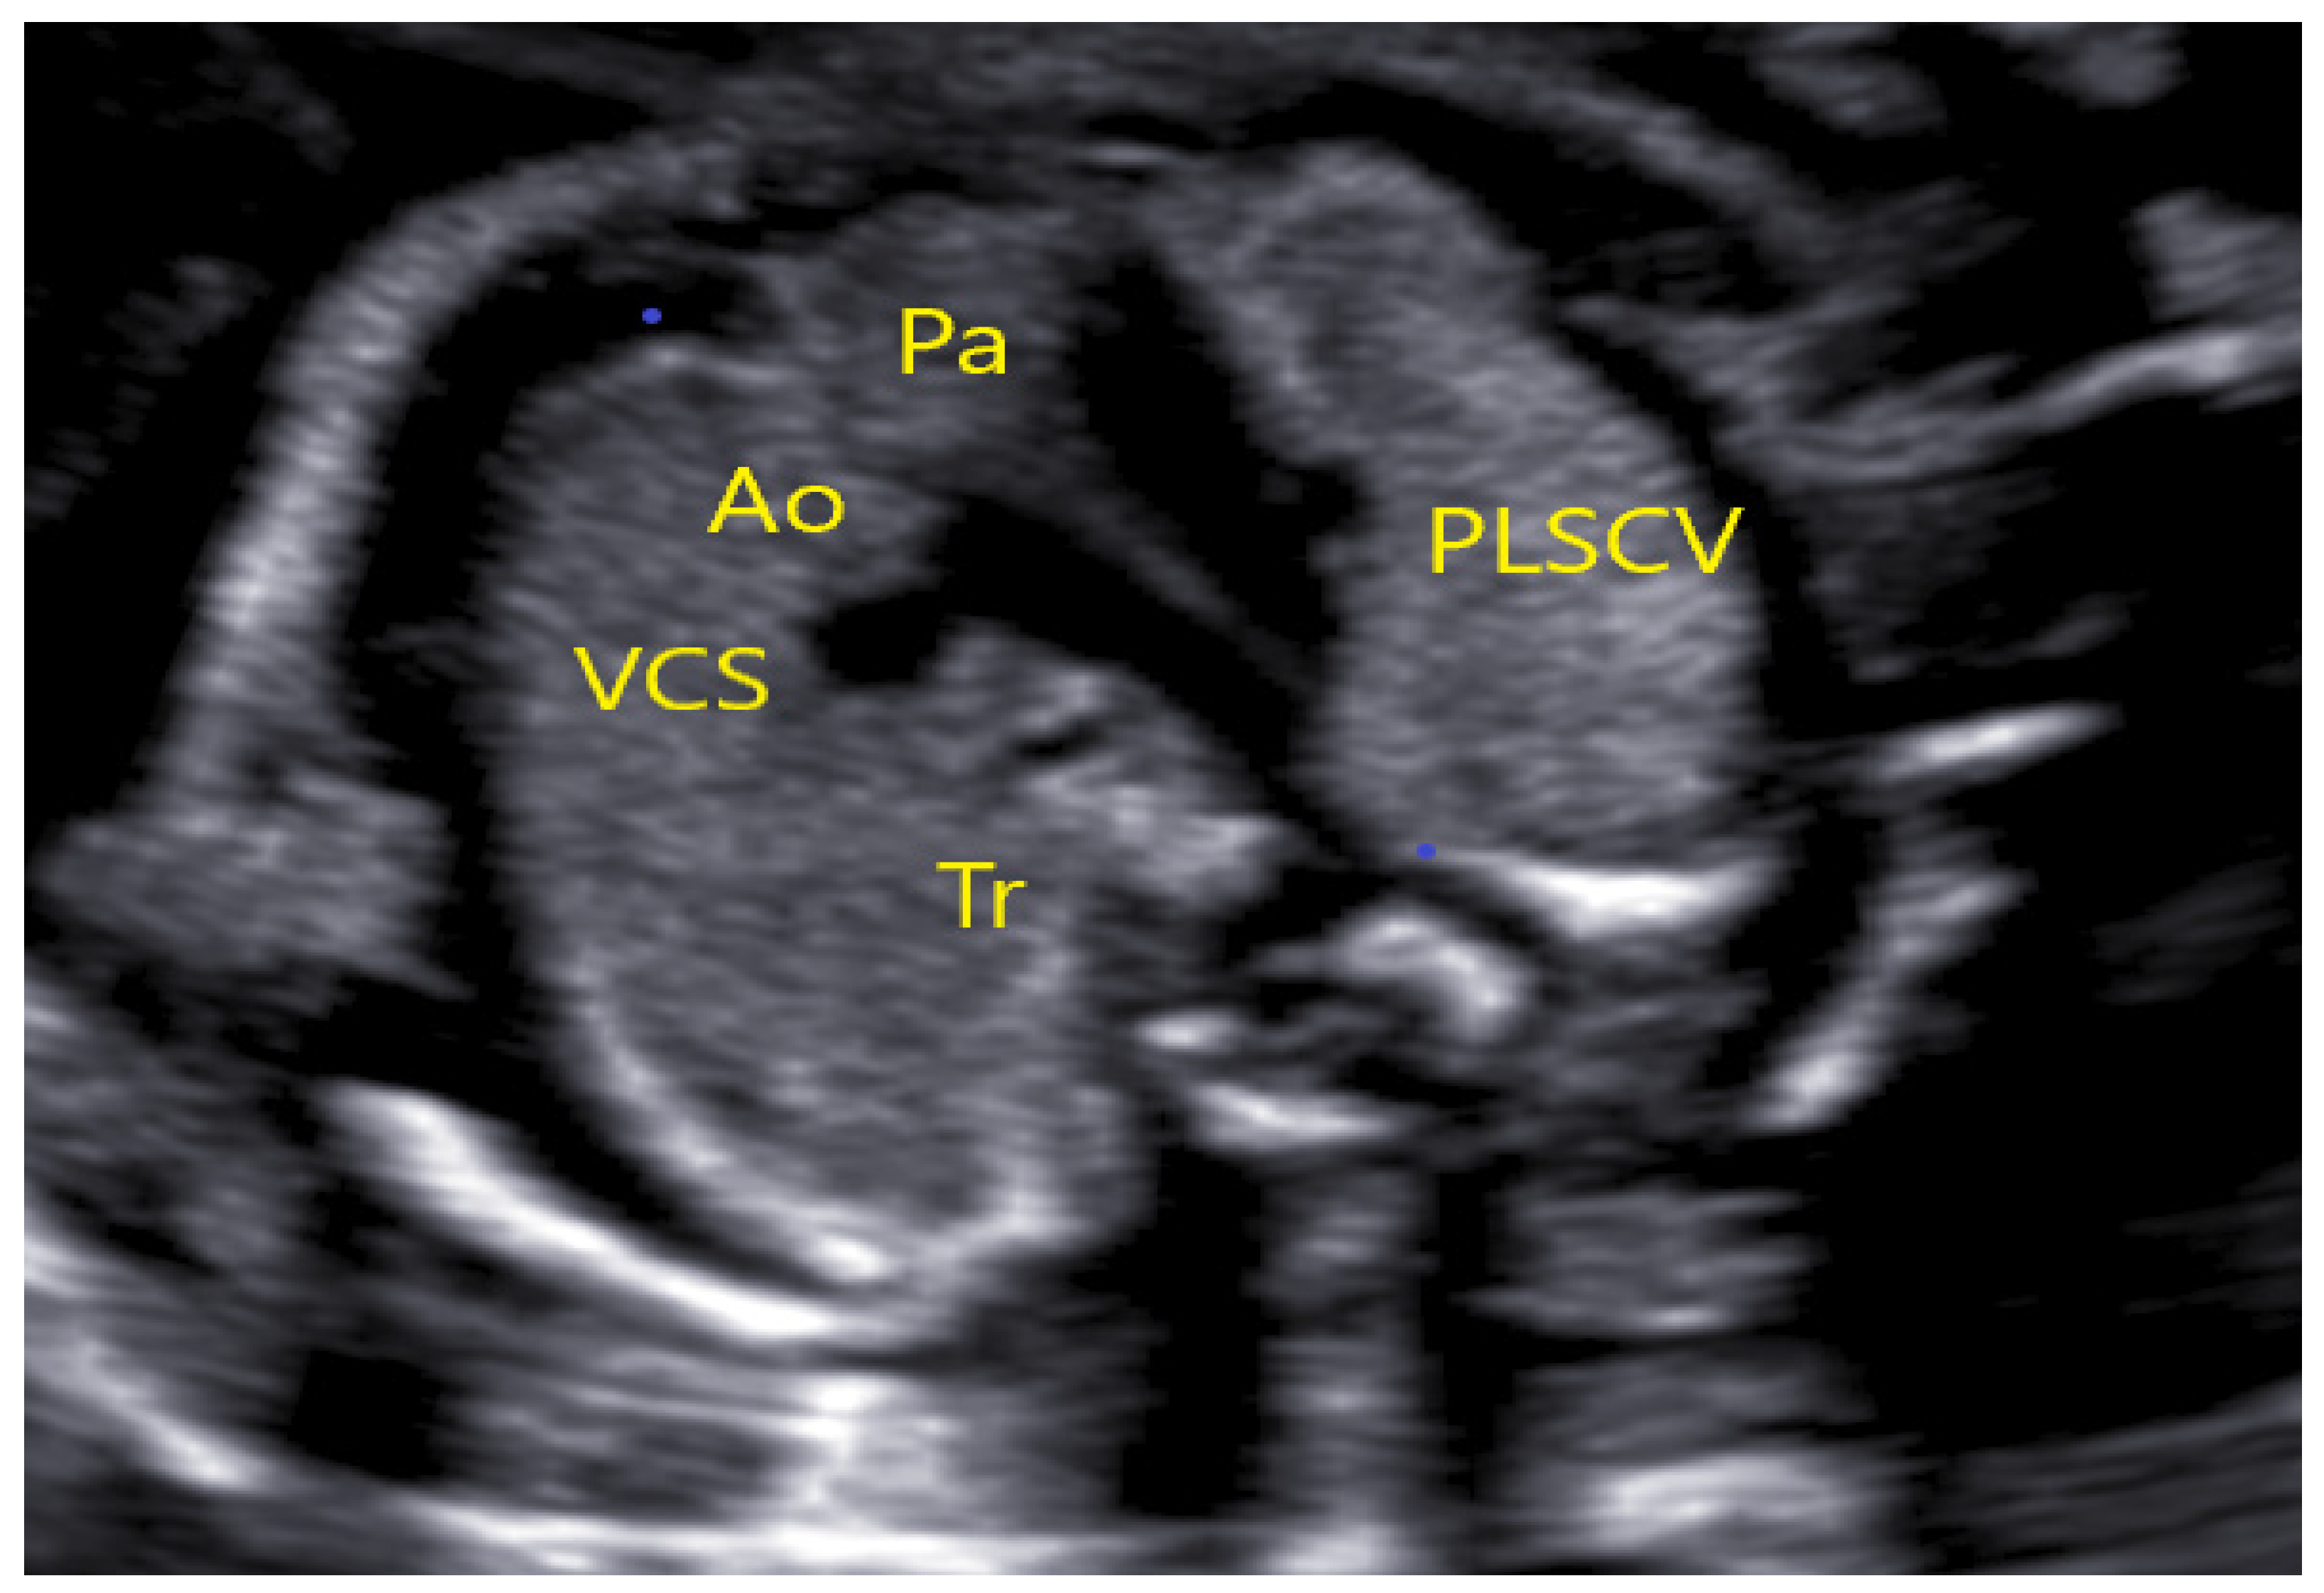

4. Cases—Ultrasound Findings Description

4.1. Case 1

4.2. Case 2

4.3. Case 3

4.4. Case 4